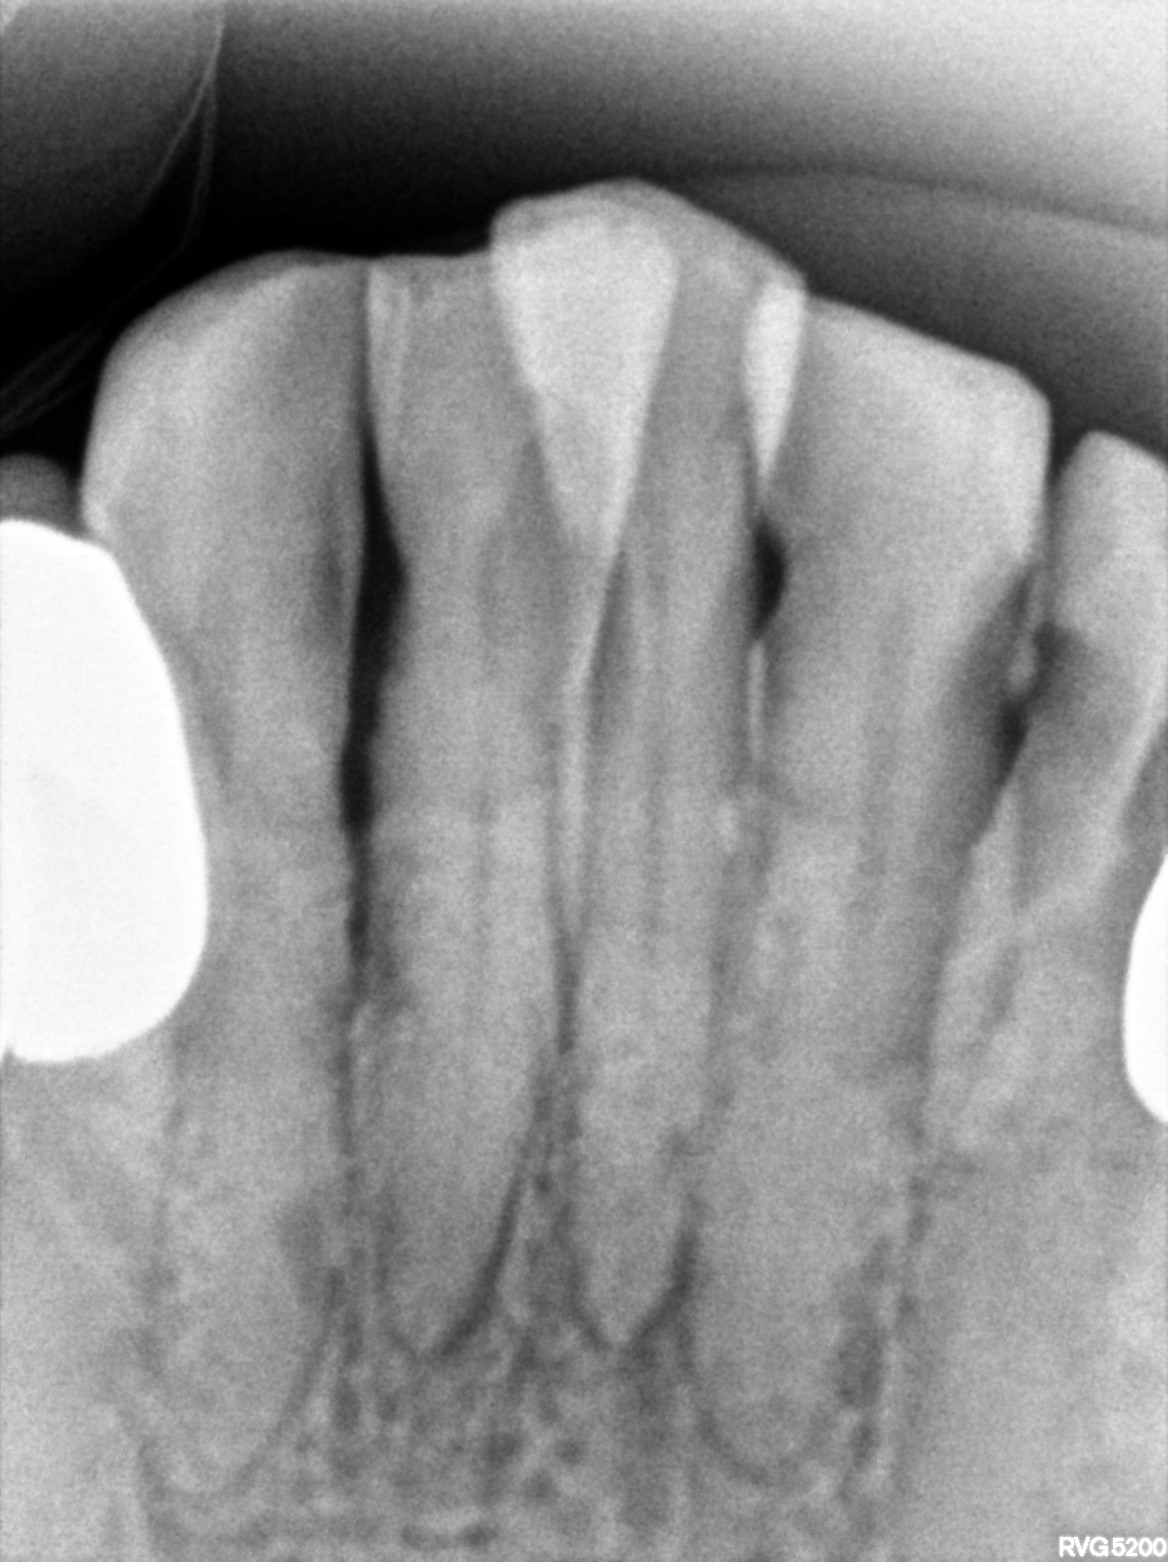

Dental Radiographs FHIR: DocumentReference · LOINC 24641-7

13 14.jpg

24641-7